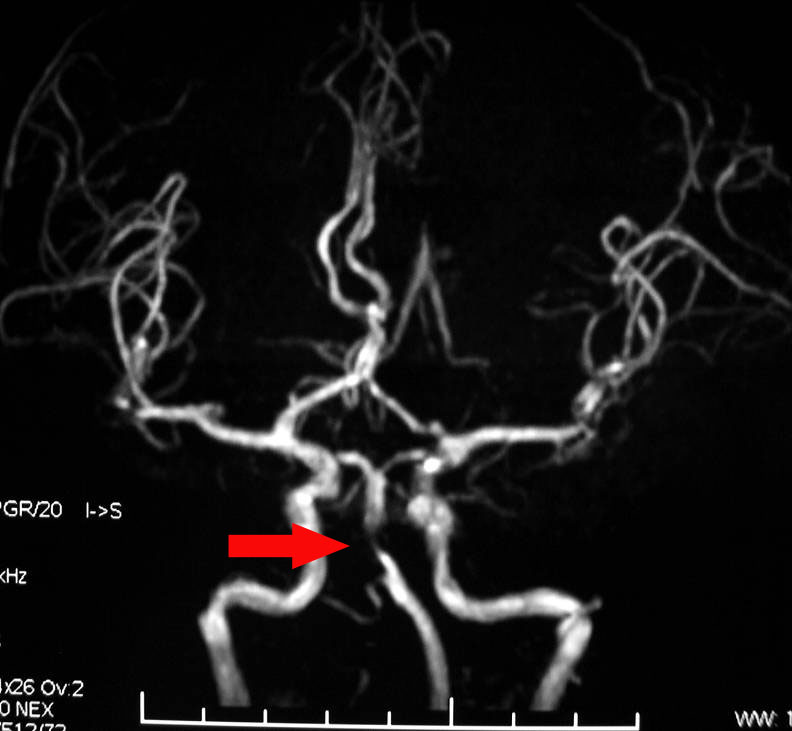

脑血管狭窄是造成缺血性脑血管病的一个重要病因和危险因素。脑血管狭窄使得经过脑血管的血液减少,脑细胞就会缺血死亡。 专家表示造成脑血管狭窄的原因很多,而且与年龄有关,如结节性动脉炎引起的血管狭窄发病年龄多在10~30岁,而由于动脉硬化狭窄者往往为40~80岁的中老年人,甚至更高年龄者。儿童发病者,多由于先天性的血管发育异常造成,颈椎病也是脑血管狭窄的诱发因素。

脑血管狭窄的症状主要有头昏、眩晕、恶心、呕吐,脑血管狭窄是各种原因引起的脑血管变细。甚至造成意识不清等,容易被误诊为“美尼尔氏综合症”此病多由高血压、高血脂、高血糖等原因引起,也有血管炎症、肿瘤等原因引起。因此一定要及时的发现和治疗。